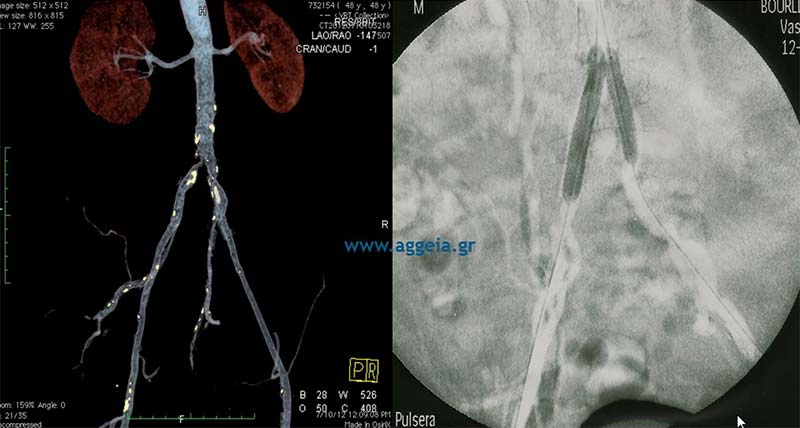

Αγγειοπλαστική λαγόνιων αρτηριών - kissing stents

Απόφραξη ΔΕ λαγονίου αρτηρίας και στένωση αριστερής - Αγγειοπλαστική με kissing stents